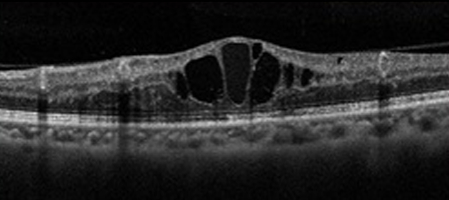

網膜の血管が詰まると、静脈から網膜に血液成分が漏れだし、出血が生じ、網膜の中心である黄斑に水があふれて腫れます。

これを黄斑浮腫と言い、網膜静脈閉塞症の視力低下の原因です。

中心静脈という網膜静脈の根元で詰まります。あふれ出た血液が網膜全体に広がります。急激な視力低下が起こり、黄斑部の浮腫が起こるとゆがみが見られ、視力も下がります。

01.黄斑部の浮腫に対しては抗VEGF薬硝子体注射

効果的ですが、効果が3か月くらいしか続かず何度も注射する場合があります。